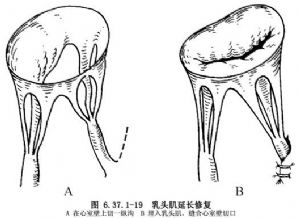

③乳头肌延长:治疗采用乳头肌缩短术,即在乳头肌上方心室壁上做一纵沟,将延长的乳头肌部分包埋其中,然后缝合切口(图6.37.1-19)。